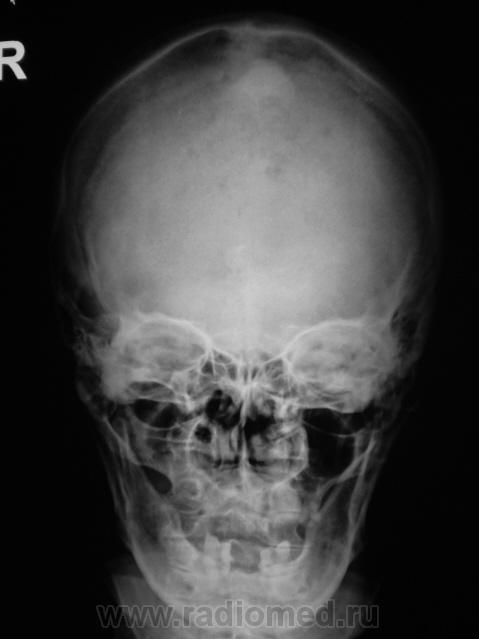

Пациентка направлена на рентгенографию черепа.

Какие будут мнения уважаемые коллеги?

Диплоические каналы и бухты. Пахионовы ямки. Брегма заросла как-то не так.

А, как быть с теми двумя "плямами" (прямая проекция), одна больше другая меньше по размерам.

Suspicio Ca dura mater.

Я конечно с головой не дружу. Но мне каца , на боковой рентгенограмме,что имеет место эндокраниальный гиперостоз лобно-теменной области с разрушением внутренней пластинки.Сиречь-опухоль.

Этот случай, в какой-то степени, аналогичен случаю, выставленному Побединским Михаилом Александровичем - "округлая тень". Это "тенеобразование", на фоне чешуи лобной кости вызвано наличием значительных размеров родинок но коже лба, и частично, волосистой части головы.